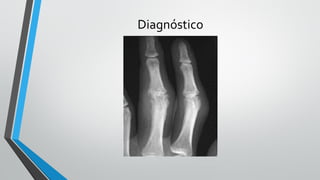

Diagnóstico

Radiologia

•Fases inicias – pode não haver alteração

•Alterações radiológicas

• Erosões justaarticulares

• Osteopenia periarticular

• Redução do espaço articular